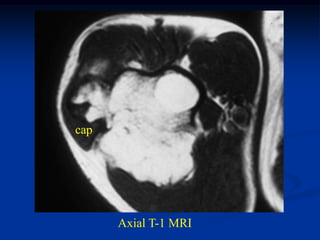

Case #608

17 year male with osteochondroma humerus

marrow

Axial T-1 MRI

cap

Sagittal T-1

MRI

Coronal T-2 MRI

Macro section